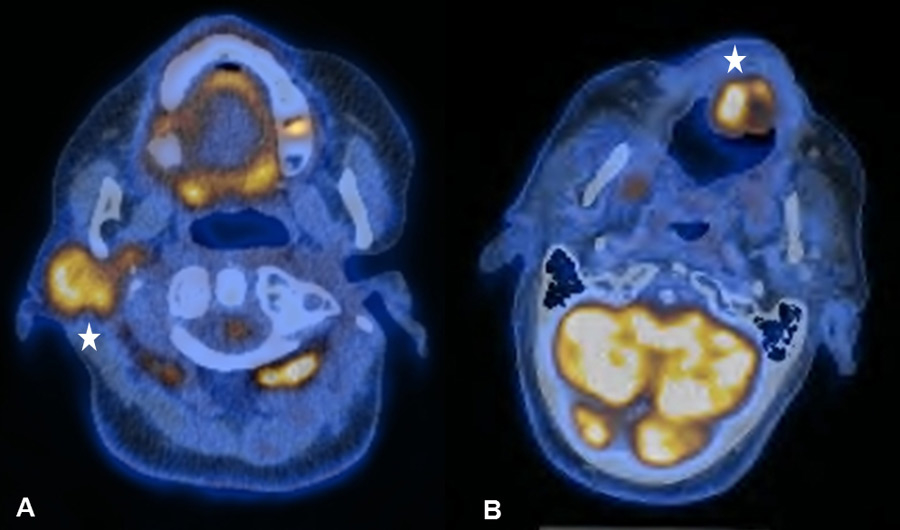

Figure 7

(A) Sixty-two year old patient after curative radio-chemotherapy (RCT) for a supraglottic larynx carcinoma with increased focal uptake in the left hypopharynx due to a radiogenic ulcer. (B) Increased focal uptake of the left mandible due to osteoradionecrosis in a 48-year old patient after curative RCT for an oropharynx carcinoma (C) Radiogenic chondronecrosis of the corniculate cartilages in a 59-year old patient after surgical resection and radiation therapy of a base of tongue carcinoma

Irradiation-related inflammatory FDG uptake was observed because of a radiogenic ulcer in the hypopharynx, osteoradionecrosis, radiogenic chondronecrosis and chronic mucosal inflammation (fig. 7ABC). The occurrence of false-positive FDG uptake caused by osteoradionecrosis in HNC patients after RT is a known difficulty and well-reported for nasopharyngeal carcinoma [34, 35]. Management of these lesions is challenging since the clinical examination can be inconclusive and definitive exclusion of malignancy often requires multiple biopsies. Re-evaluation by a multidisciplinary tumour board plays a pivotal role in adequate management of these challenging patients: surgeons, nuclear medicine physicians, radiation oncologists, oncologists and pathologists need to carefully review indistinct findings and to determine individual diagnostic algorithms.